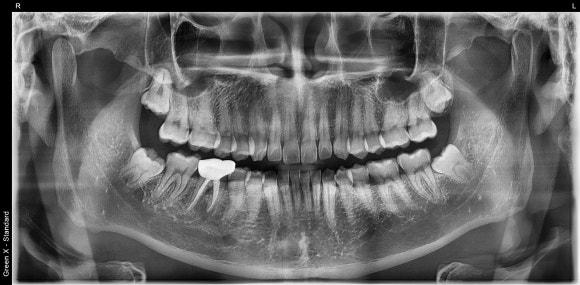

올 초 저에게 오신 30대 남성분입니다.

전반적으로 치아 관리 상태가 매우 우수합니다.

오른쪽 아래 치아에

불과 6개월 전에 신경치료를 받으셨다고 합니다.

그간 아프진 않았지만,

어느 날 잇몸으로 고름주머니가 불거진 것을 확인하셨다고 합니다.